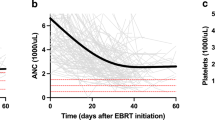

The hematological data, including WBC, hemoglobin concentration and platelet count were recorded from laboratory studies performed under CRT. All available information about the relevant acute therapy side effects according CTCAE and RTOG criteria (nausea, leucopenia, anemia, thrombopenia, loss of weight, diarrhea, skin reaction, fatigue, vaginal mucositis, urological side effects) were assembled out of the patient files. For the correlation of the blood levels the nadir of WBCs, hemoglobin levels and thrombopenia during CRT were analyzed.

Hematologic toxicity

Regarding information about the relevant acute and late therapy side effects three patients had a grade 4 acute toxicity according to CTCAE criteria for leukopenia (n = 2) and diarrhea (n = 1). Grade-3 acute toxicity existed for leukopenia (n = 17), anemia (n = 5), thrombopenia (n = 3), diarrhea (n = 2), nausea (n = 6), vaginal bleeding (n = 1) and dysuria (n = 2). Except for one patient suffering from grade-3 loss of weight (according to late toxicity RTOG criteria) only grade 1 and 2 late toxicities occurred.

Correlation of blood levels and PB and FH constraints

Comparing the absolute blood levels with the dose volumes of both FH and PB the data showed a significant correlation between WBC and the median dose of the FH and the median dose, V30Gy, V40Gy and V50Gy of the PB (Table 2). A correlation between the toxicity grade of anemia and mean dose, maximum dose and V5Gy of the PB was found. Counting the highest grade of HT of all three blood levels of each patient, significant correlations were found for the mean and median dose, V30Gy, V40Gy and V50Gy of the PB. Further dosimetric details of BM subsites are presented in Table 3.

In our analysis of cervical cancer patients undergoing CRT with IG-VMAT, we were able to identify a defined subset of BM dose–volume parameters that seem to correlate with different forms of HT. Notably, intermediate and higher doses (subvolumes receiving 30–50 Gy) of the PB had a negative impact on WBC and mean dose as well as lower doses (V5Gy) lead to higher HT in terms of anemia. Correlations of the dose–volume parameters with HT according to CTCAE by logistic regression failed to show any correlation. Scatter plots though showed an apparent correlation with a tendency to higher toxicity grades with higher radiated dose volumes so that probably a larger patient cohort is necessary to show a significance.